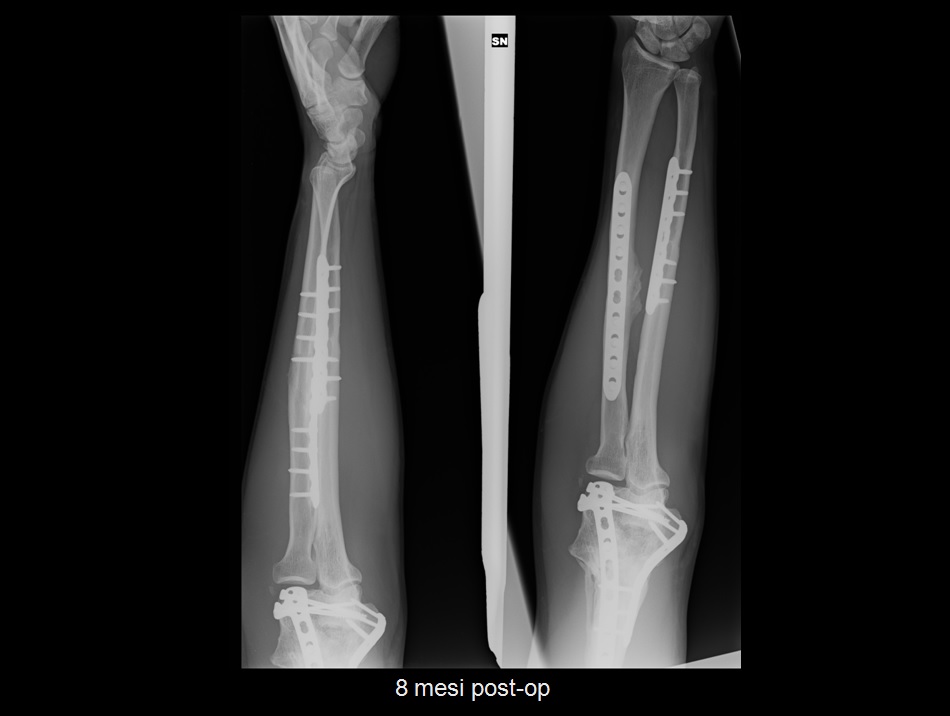

Frattura scomposta Capitello Radiale

Frattura scomposta Capitello Radiale from 4.bp.blogspot.com